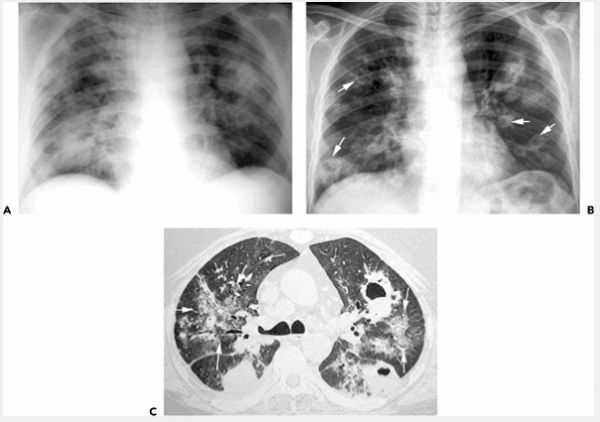

A: X quang ngực thẳng trước sau cho thấy khu vực song phương hợp nhất.

B: X quang 6 ngày sau cho thấy nhiều ổ áp xe hình thành và cavitation (mũi tên).

C: Chụp cắt lớp vi tính độ phân giải cao (CT) (1 mm chuẩn), hình ảnh ở mức độ phế quản chính cho thấy trọng tâm nhiều hợp nhất, một số trong đó được cavitated. Cũng ghi nhận được chắp kính song phương Opacity với chồng Opacity tuyến tính (mũi tên) và tràn dịch màng phổi phải nhỏ. Bệnh nhân đàn ông 45 tuổi.